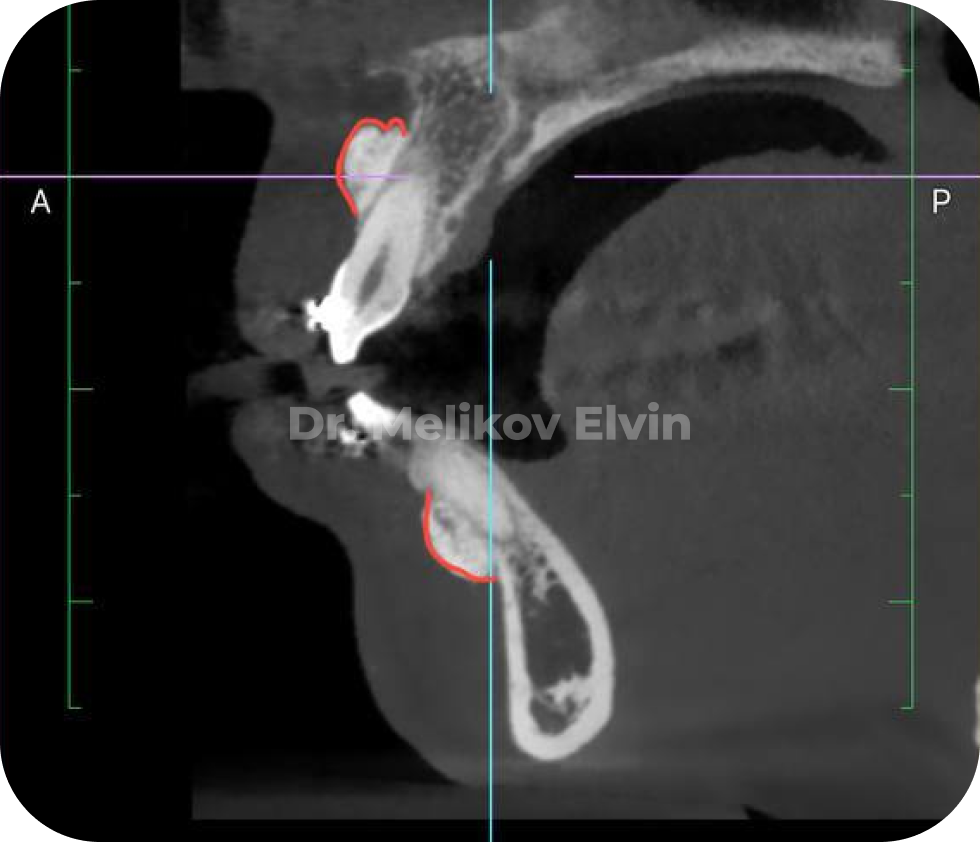

На снимках можно увидеть воссозданный объём наружной кортикальной пластинки в проекции корней зубов.

После костной пластики на двух челюстях